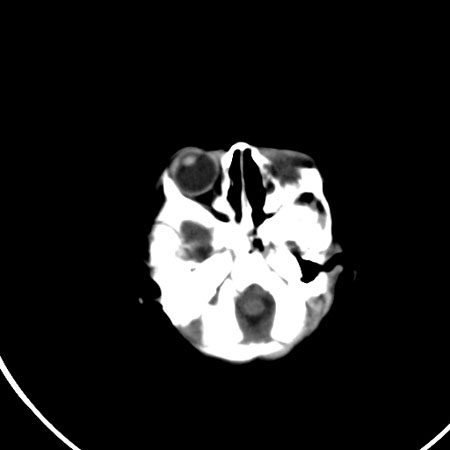

以下是引用小初学者在2009-1-10 17:51:00的发言:[br]考虑缺血缺氧性脑病后遗性改变。

以下是引用拾荒者在2009-1-10 19:23:00的发言:[br]生后有蛛网膜下腔出血病史,现幕上脑室明显扩张,脑室周围白质局限性密度减低,考虑hie脑病后遗表现。